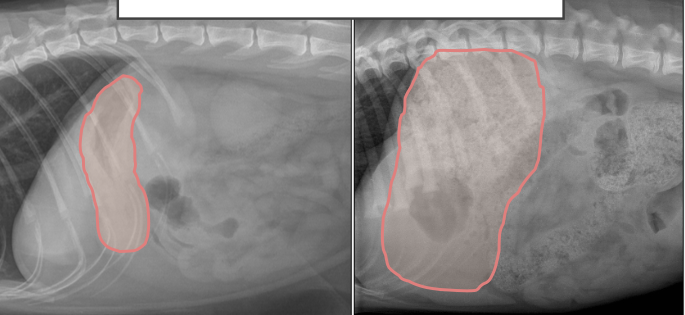

Dire quelle image de l’estomac correspond à un chat et laquelle correspond à un chien

à droite = chat

à gauche = chien

*Chez le chien, l’estomac a une forme moins repliée et l’antre pylorique se retrouve à droite. Chez le chat, l’estomac a une forme de « U » abrupte et l’antre pylorique reste généralement plus proche de la ligne médiane de l’abdomen.

Tracez l’endroit où se trouve l’estomac sur ces radio

Tracez à quel endroit se trouve l’estomac sur ces radio